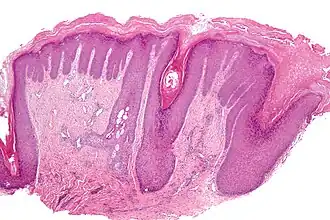

L'hyperkératose est un terme général qui, dans le domaine de la dermatologie, désigne un groupe d'affections de la peau caractérisées par une augmentation significative de la kératinisation, et de ce fait une augmentation de la couche cornée de l'épiderme : ichtyose, kératose (kératodermie), porokératose, verrue[1].

L'inflammation peut augmenter le processus de renouvellement cellulaire des kératinocytes. Ce mécanisme de défense va entraîner un déséquilibre entre "création" et "élimination". Les cellules mortes chargées en kératine vont donc être en surnombre et finissent par se compacter pour former des blocs de kératine, c'est l'hyperkératose. Cette hyperkératose aura des aspects bien différents en fonction de l'étiologie, de la localisation, et du type de peau concerné.